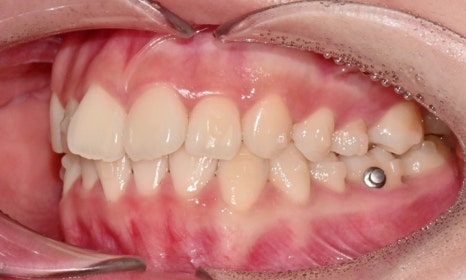

2025.3. 초진 (앞니 경미한 총생과 과개교합) - 연세정원치과

정밀진단 결과 위아래 앞니가 약간 겹쳐 있어 배열이 고르지 않은 상태였으며, 약간의 과개교합이 동반된 상태였습니다. 다만 골격적인 문제나 안모 불균형은 없었고, 측면에서도 돌출감 없이 비교적 안정적인 안모를 유지하고 있었습니다.

이러한 점을 종합적으로 고려해보았을 때 치아 배열의 개선과 교합 조정을 중심으로 한 비발치 교정 치료가 적합한 케이스였습니다. 또한 환자가 고등학생이라는 점, 그리고 학업과 일상 생활에 대한 부담을 최소화하고 싶다는 보호자의 의견을 반영하여, 인비절라인으로 선택하게 되었습니다.

이번 케이스는 인비절라인 Comprehensive로 치료를 진행하였으며, 치아 이동은 과도하지 않게 단계적으로 진행하기 위해 치간삭제를 최소한으로 적용하며 공간을 확보하는 방향으로, 총 33단계의 장치를 통해 치아 이동을 계획하였습니다.